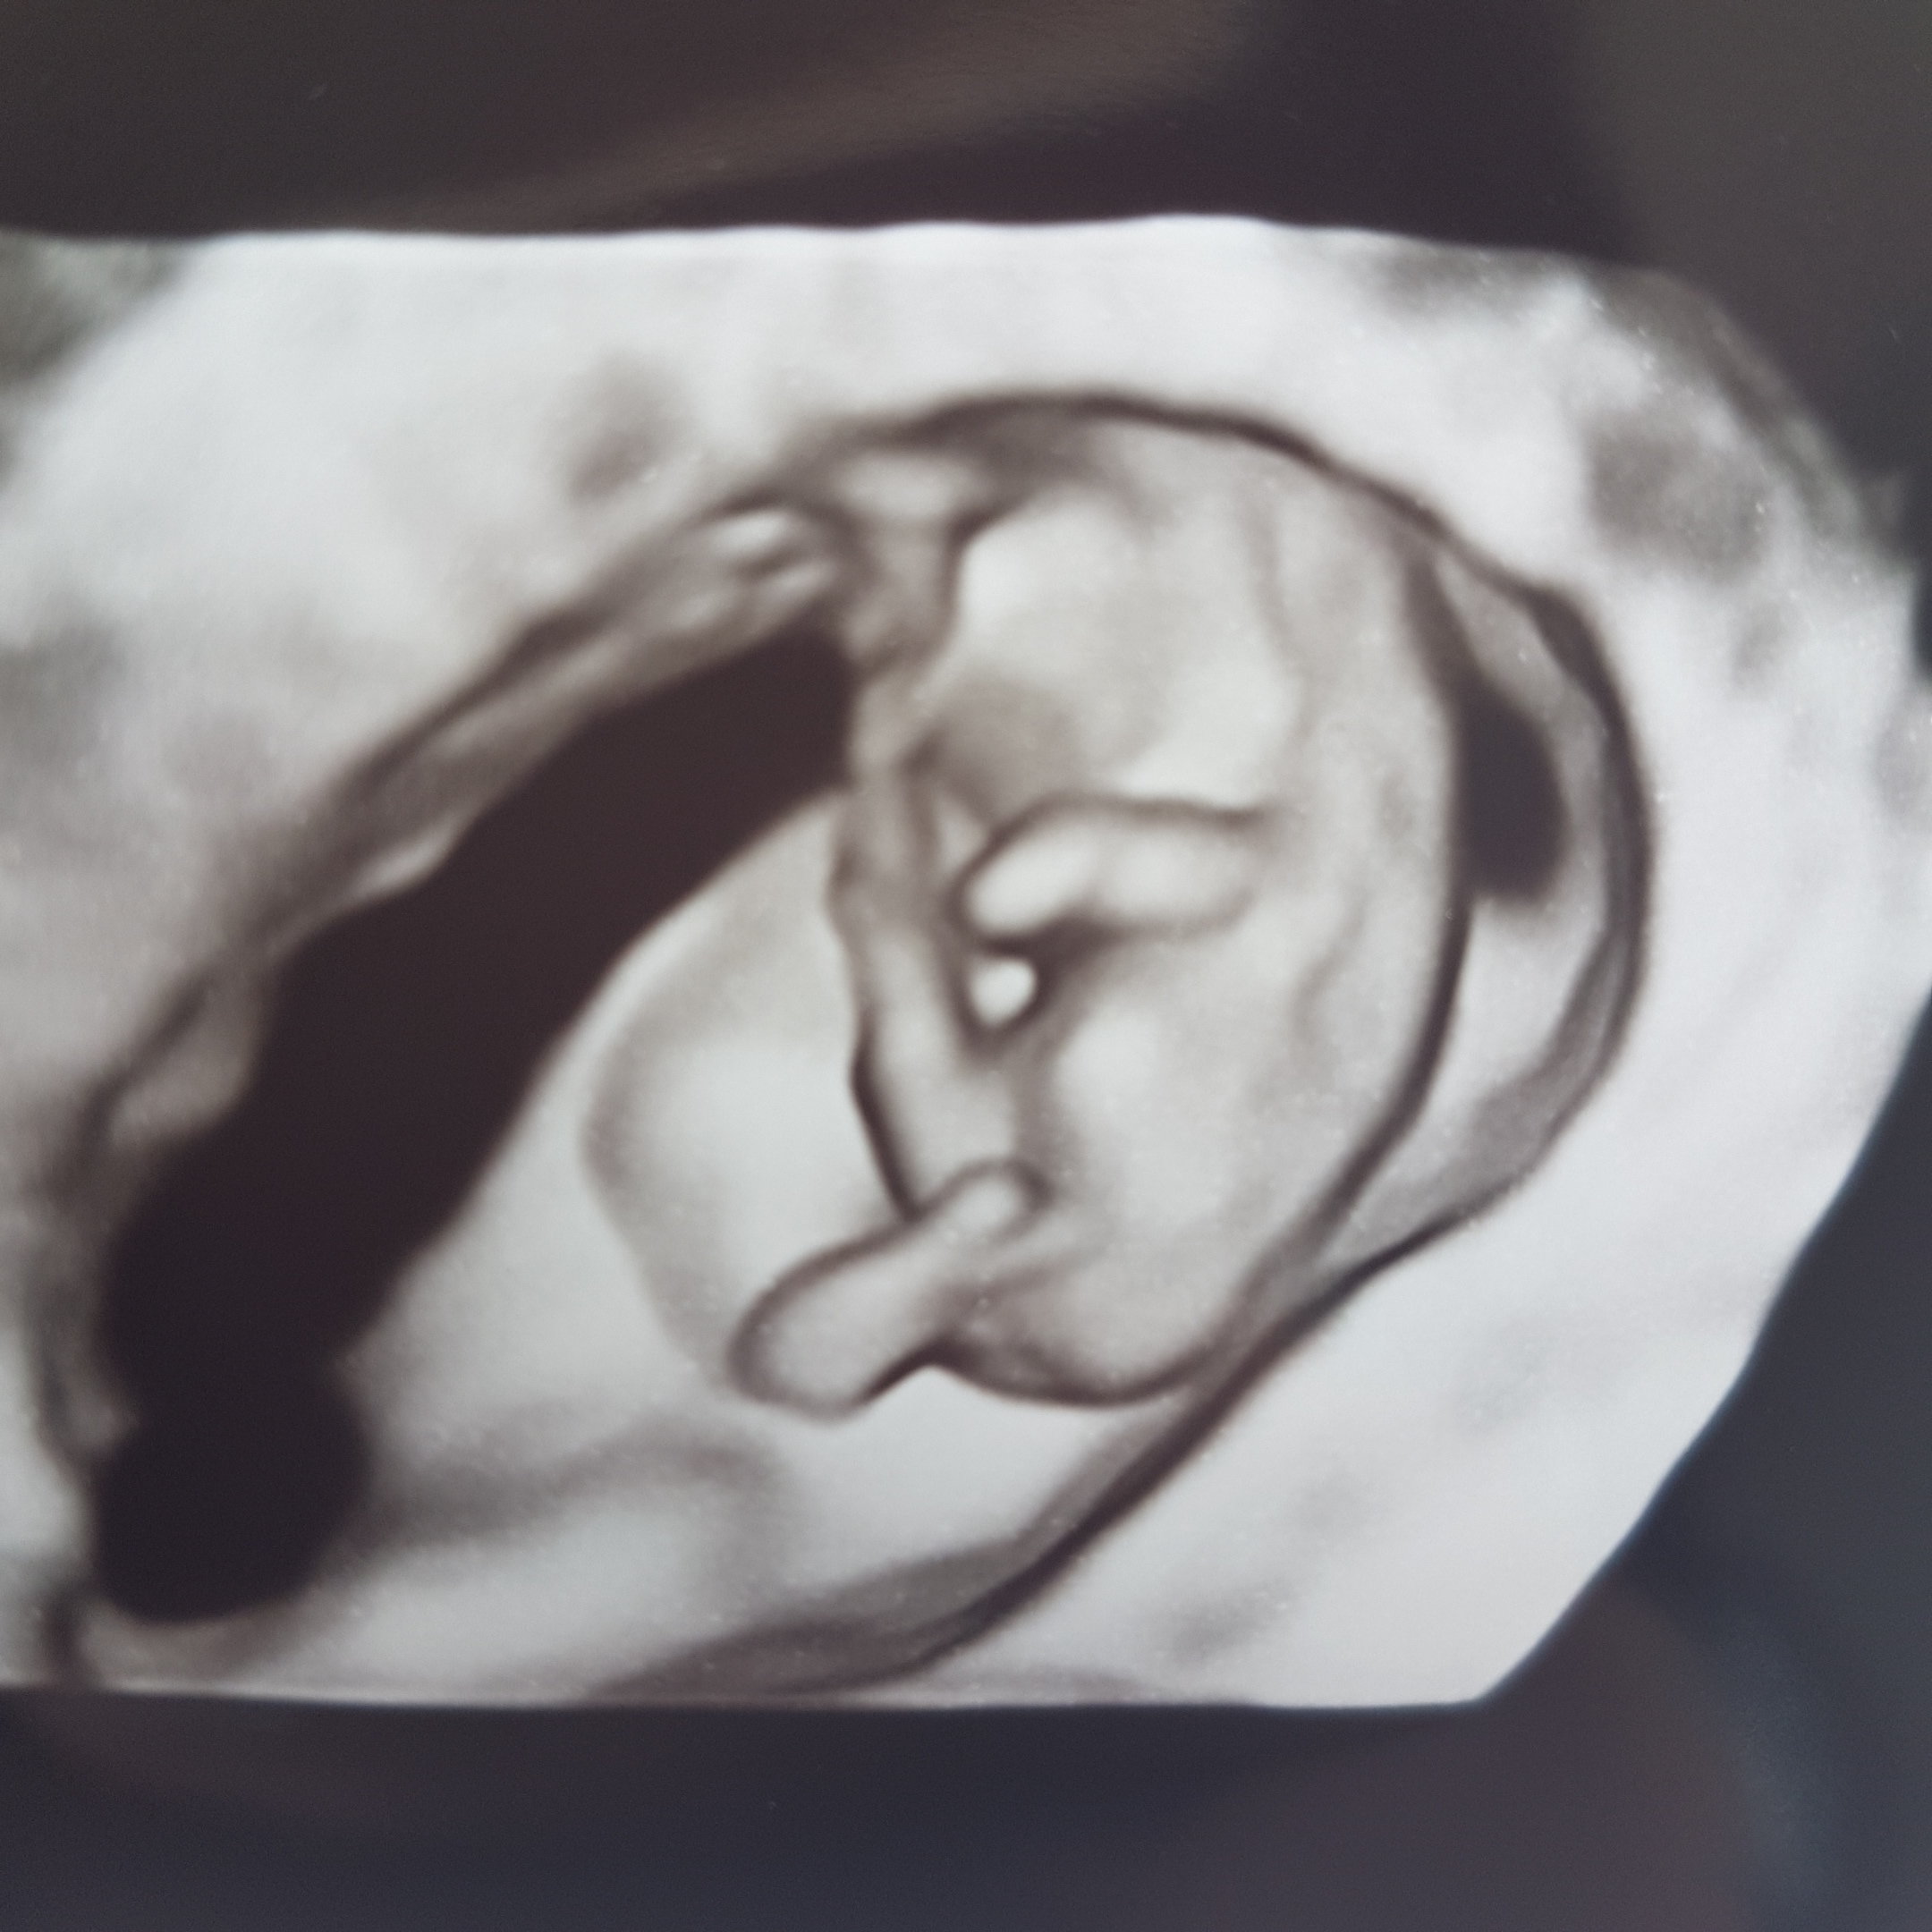

Tez widzę krokodyla [emoji6]Nie wiem jak wy, ale ja tam widzę małego krokodyla.

A tak serio to śliczna młodzież się rozwija.

6.89cm [emoji7] Franek !! [emoji4]